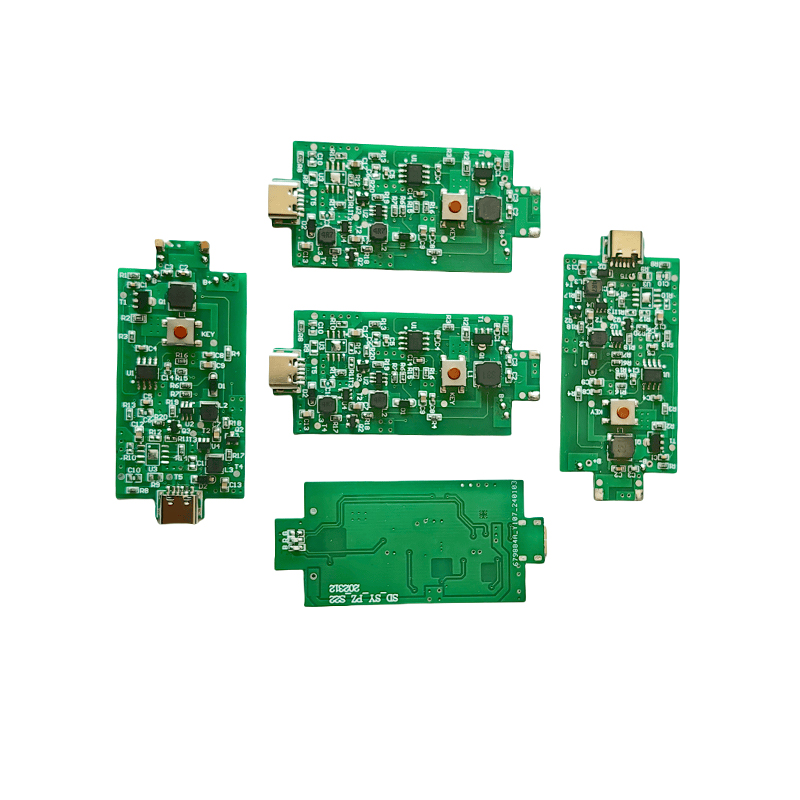

أقراص البخاخات الشبكية الطبية هي مكونات دقيقة تستخدم في الأجهزة الطبية لتحويل الأدوية أو المحاليل إلى جزيئات صغيرة من الهباء الجوي لعلاج اضطرابات الجهاز التنفسي المختلفة مثل الربو ومرض الانسداد الرئوي المزمن (COPD) وما إلى ذلك عن طريق الاستنشاق. يعد التصميم واختيار المواد لطبقة البخاخات أمرًا بالغ الأهمية لضمان توصيل الدواء بشكل فعال وراحة المريض. يتم ثقب ورقة الحجاب الحاجز غير القابل للصدأ بآلاف من الثقوب الشبكية الصغيرة مقاس 2-3 ميكرومتر في الصفائح الفولاذية من خلال تقنية الحفر بالليزر في عملية ليزر دقيقة، ومن ثم يتم ربطها بإحكام مع الصفائح المستديرة الخزفية الكهرضغطية، والتي تحول تردد الرنين للصفائح الكهرضغطية إلى طاقة اهتزاز عالية التردد من خلال إشارة الخرج للوحة تشغيل PCB، وتكسر بسرعة الدواء السائل إلى جزيئات الهباء الجوي الدقيقة. وتسمى هذه القطرات أيضًا بحجم الجسيمات المتوسطة، عندما تصل نسبة حجم الجسيمات المتوسطة D50 إلى> 60% أو أكثر، ستكون الجسيمات صغيرة بما يكفي لتتمكن من الوصول إلى عمق الرئتين إلى سطح الحويصلات الهوائية مع التنفس، وبالتالي تحسين كفاءة امتصاص الدواء والتأثير العلاجي. تحتوي صفائح البخاخات الشبكية الطبية الدقيقة بشكل أساسي على عدة أشكال، ورقة البخاخات الشبكية الدقيقة المصنوعة من الفولاذ المقاوم للصدأ، ورقة البخاخات الطبية بالنيكل والبلاديوم، ورقة البخاخات الطبية بوليمر PI، وما إلى ذلك. كل ما سبق يتم من خلال تحويل طاقة الاهتزاز الخزفي الكهرضغطي لتحقيق تأثير الانحلال.

بوليميد (بوليميد) يشار إليه باسم PI، هو أفضل أداء شامل لمواد البوليمر العضوية، وله ثبات كيميائي ممتاز، ويمكنه تحمل التآكل الناتج عن مجموعة متنوعة من الأدوية، لضمان الاستخدام طويل الأمد لأداء الأقراص المذرية. بالإضافة إلى ذلك، فإن الثبات الحراري لفيلم البوليمر PI ممتاز أيضًا، مع الاستخدام طويل الأمد لنطاق درجة الحرارة -200 ~ 300 درجة مئوية، والعزل العالي، وحماية البيئة، وغير السمية، كمواد هندسية خاصة، تستخدم على نطاق واسع في أغشية الفصل البلوري السائل النانوي للإلكترونيات الدقيقة وغيرها من المجالات، وقد تم تضمينها في القرن الحادي والعشرين من قبل بلدان واحدة من أكثر المواد الهندسية الواعدة، وليس من السهل أن تكون مشوه أثناء عملية التطهير بدرجة الحرارة العالية، لضمان إعادة استخدام المنتج! من أجل الجنس والسلامة، نستخدم تقنية الليزر لثقب الليزر، وفيلم PI مزروع بين الفولاذ المقاوم للصدأ والصفائح الكهرضغطية، واستخدام تقنية الموجات فوق الصوتية الخزفية الكهرضغطية بحيث تتوزع القطرات المتناثرة من خلال فيلم PI إلى ذرات من جزيئات 3 ~ 4 ميكرومتر لاستنشاق البخاخات الطبية، وهي سلامة غالبية المستخدمين الذين يحبونها، مصنوعة من البخاخات مع الميزة الرئيسية لـ PI هي عدم الانسداد، والجدار الداخلي للفتحة أملس ومستدير، ولا يوجد بقايا للسائل، والانحلال دقيق ومستقر. الانحلال دقيق ومستقر. أقراص البخاخات ذات الفيلم PI يمكنها أن تمنع بشكل فعال بقايا الأدوية، وتقلل من خطر التلوث المتبادل. في التطبيق العملي، انعكست أيضًا خصائص استهلاك الطاقة المنخفضة لأقراص البخاخات ذات غشاء البوليمر PI، باختصار، أصبحت أقراص البخاخات ذات غشاء البوليمر PI مع أدائها الممتاز ومزايا التصميم، جزءًا لا غنى عنه في مجال علاج البخاخات الطبية.

يُعرف السيراميك الكهرضغطي الخالي من الرصاص باسم "لؤلؤة" صناعة الكهرضغطية، وسيحل المستقبل تدريجيًا محل السيراميك الكهرضغطي القائم على الرصاص في جميع الجوانب، والذي يتمتع بالفعل بنفس الأداء الكهرضغطي، والصفائح الكهرضغطية القائمة على الرصاص. إنها غير سامة تمامًا وغير ضارة وآمنة وصديقة للبيئة، ولا تحتوي على الرصاص والأنتيمون والمعادن الثقيلة الأخرى وغيرها من العناصر المقيدة بـ Rohs، درجة حرارة كوري عالية Tc-328 درجة مئوية، وفقدان كهربائي منخفض جدًا TangentLoss ولذلك، فإن رقاقة الانحلال الطبي الكهرضغطية الخالية من الرصاص لها قيمة تجارية كبيرة وقيمة عالمية، والسيراميك الكهرضغطي غير سام وصديق للبيئة وخالي من الرصاص بالإضافة إلى الأداء غير الملوث والكهرضغطي الذي يتناسب مع السيراميك القائم على الرصاص، سوف يصبح سيراميك كهرضغطية صديق للبيئة مشهورًا. بعد سنوات من البحث والتطوير، وبعد الاختبار المستمر والتجربة، نجحت الشركة في صنع شريحة الانحلال الطبي الخالية من الرصاص لتحقيق نفس كمية الانحلال مثل شريحة الانحلال المعتمدة على الرصاص، ونفس متطلبات جسيمات القطر. شريحة البخاخات الشبكية الطبية الخالية من الرصاص، سوف تتألق بالتأكيد وستحصل على مجموعة واسعة من سيناريوهات الاستخدام.